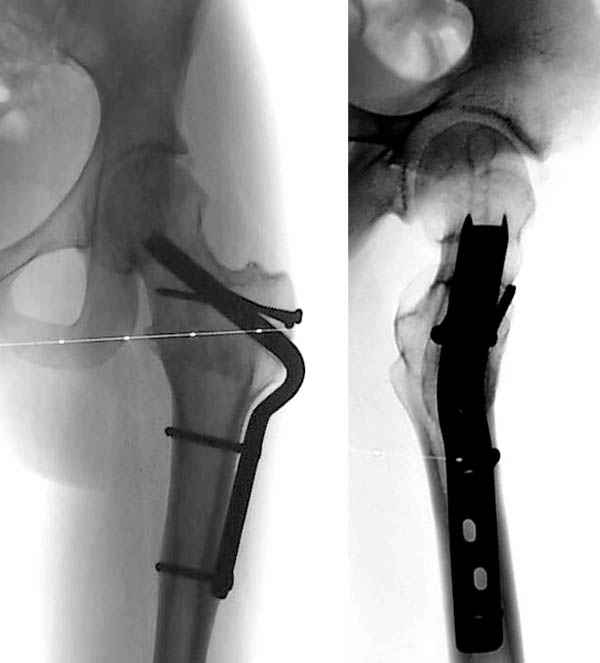

Позвольте представить Вашему вниманию вариант компоновки аппарата. Подробно методика закрытой декомпрессии тазобедренного сустава в сочетании с пролонгированной стимуляцией процессов остеогенеза описана в книге ШевцоваВ.И., Макушина В.Д. "Остеохондропатия тазобедренного сустава: Руководство для врачей". - М:ОАО "Издательство "Медицина", 2007.

Откуда и взят прилагаемый рисунок.

Юрий Алексеевич Булахтин

Здесь представлен один из случаев остеотомии на шейке после остаточного явления юношеского эпифизиолиза из Flip Trochanteric доступа.

Djoldas Kuldjanov, MD